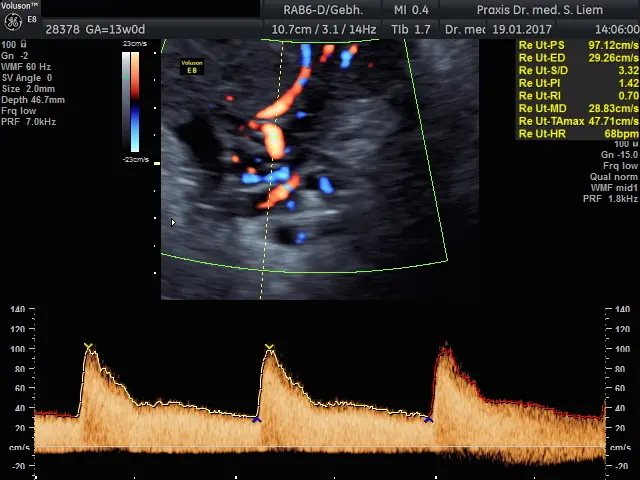

Man geht davon aus, dass Aspirin die Präeklampsie durch Verbesserung der Plazenta-Durchblutung verhindert. Die genaue Wirkungsweise ist jedoch noch nicht vollständig geklärt.